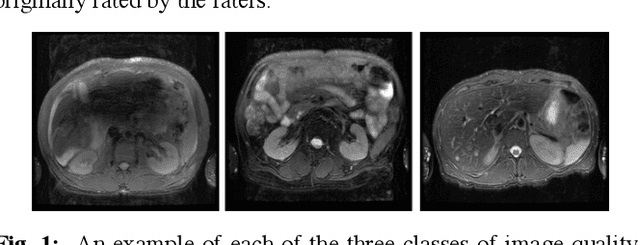

Abstract:Magnetic Resonance Imaging (MRI) suffers from several artifacts, the most common of which are motion artifacts. These artifacts often yield images that are of non-diagnostic quality. To detect such artifacts, images are prospectively evaluated by experts for their diagnostic quality, which necessitates patient-revisits and rescans whenever non-diagnostic quality scans are encountered. This motivates the need to develop an automated framework capable of accessing medical image quality and detecting diagnostic and non-diagnostic images. In this paper, we explore several convolutional neural network-based frameworks for medical image quality assessment and investigate several challenges therein.